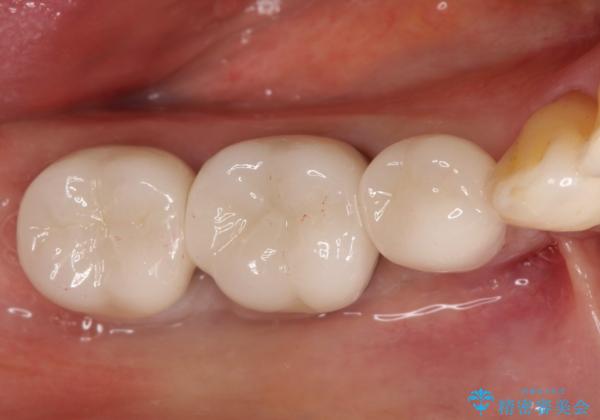

虫歯の治療 オールセラミッククラウン

- 他院にて以前治療した修復物の下に虫歯を認めたため、オールセラミックにて修復治療を行なっております。

オールセラミッククラウンは天然歯と同様に透明感を出すことができ、より審美的な治療が可能です。